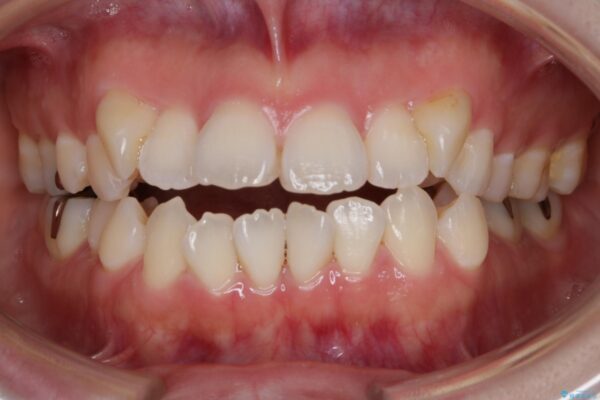

来院動機

前歯のガタつき、噛み合わせの不調を改善したいとご来院されました。

オープンバイト